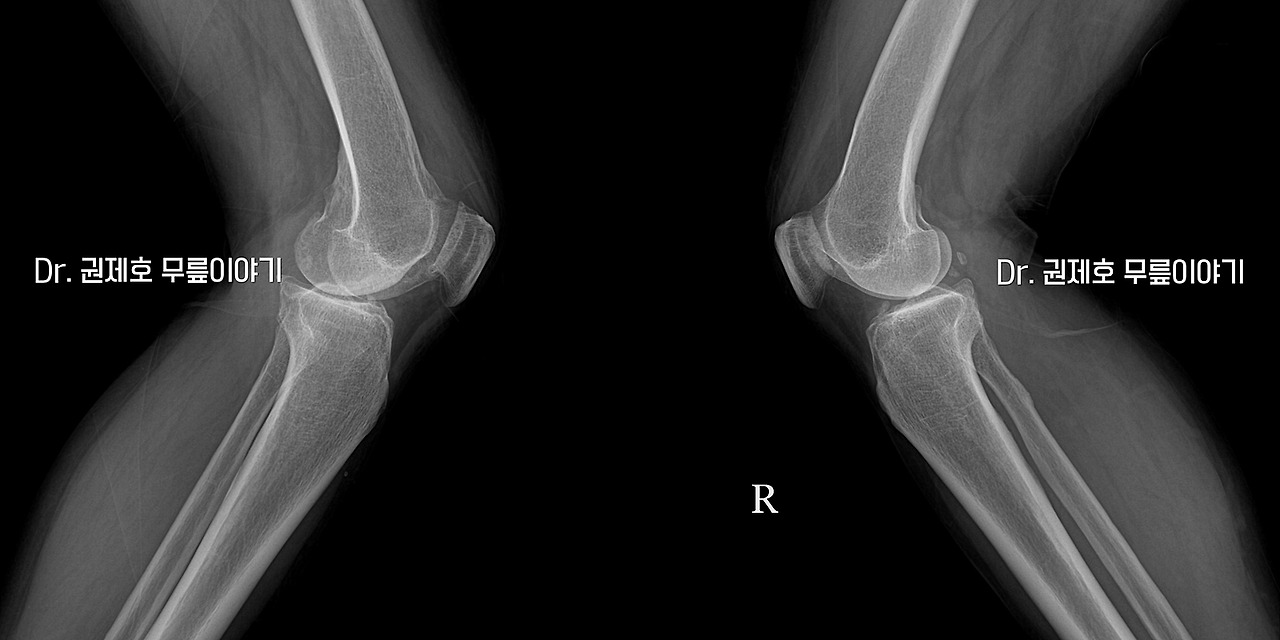

양 옆에서 촬영한 검사를 보면 왼쪽과 오른쪽 특별한 차이는 없었다.

기존 무릎의 변화된 정렬을 다시 잘 맞췄는지 슬개골의 위치를 보고도 다시 확인한다.